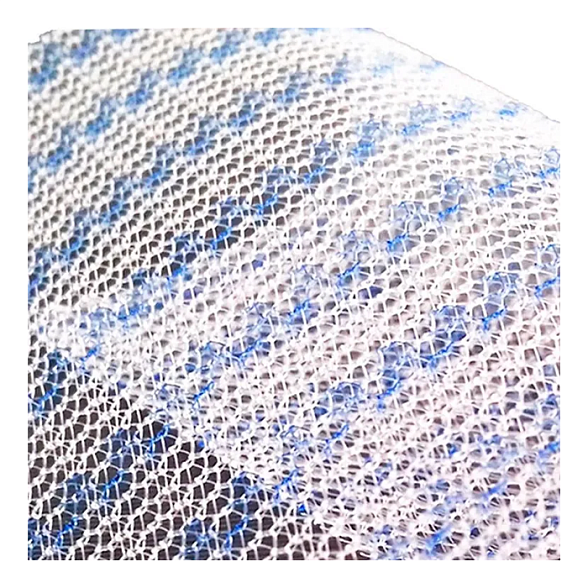

Эндопротез-сетка (сетка хирургическая) полипропиленовый для восстановительной хирургии ЭСФИЛ тяжелый, 8х12 см, Линтекс

Эндопротез-сетка полипропиленовая ЭСФИЛ тяжелый для восстановительной хирургии

Представляем вашему вниманию высококачественный хирургический имплантат — эндопротез-сетку полипропиленовую ЭСФИЛ тяжелый от известного производителя «Линтекс». Это современное решение для пластики и укрепления тканей в абдоминальной и тазовой хирургии, разработанное для обеспечения надежного и долговечного результата.

Сетка ЭСФИЛ тяжелый размером 8х12 см — это монофиламентный полипропиленовый сетчатый эндопротез с увеличенной плотностью и массой. Его ключевая особенность — высокая механическая прочность при минимальной ригидности, что позволяет эффективно закрывать обширные дефекты тканей, обеспечивая физиологичное и анатомичное восстановление.

- Отличная интеграция с тканями: Макропористая структура монофиламентной сетки способствует свободному прорастанию соединительной ткани, обеспечивая прочное сращение и снижая риск осложнений.

Благодаря макропористой структуре (размер пор более 75 мкм) сетка свободно инфильтрируется макрофагами, фибробластами и коллагеновыми волокнами. Это приводит к образованию прочного соединительнотканного рубца, который и составляет основу несущего каркаса.